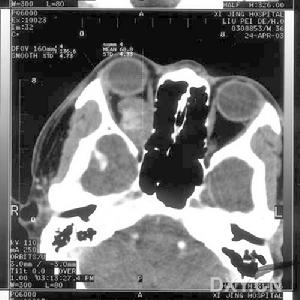

(3)CT掃描 可以發現不規則形狀的中密度腫物和繼發水腫、浸潤引起的眼外肌肥大,可呈局限性增粗,形狀不規則,內直肌較其他眼外肌更易受累。眼環增厚,浸潤性腫塊邊緣不清或結節狀,均勻或不均勻強化,視神經增粗,眶骨受累,可被CT發現溶骨現象。對於眶內轉移癌均應進行顱腦掃描,因眶內結構與顱內結構同由頸內動脈供血,且腦供血更為豐富,發生轉移癌的可能性更大。